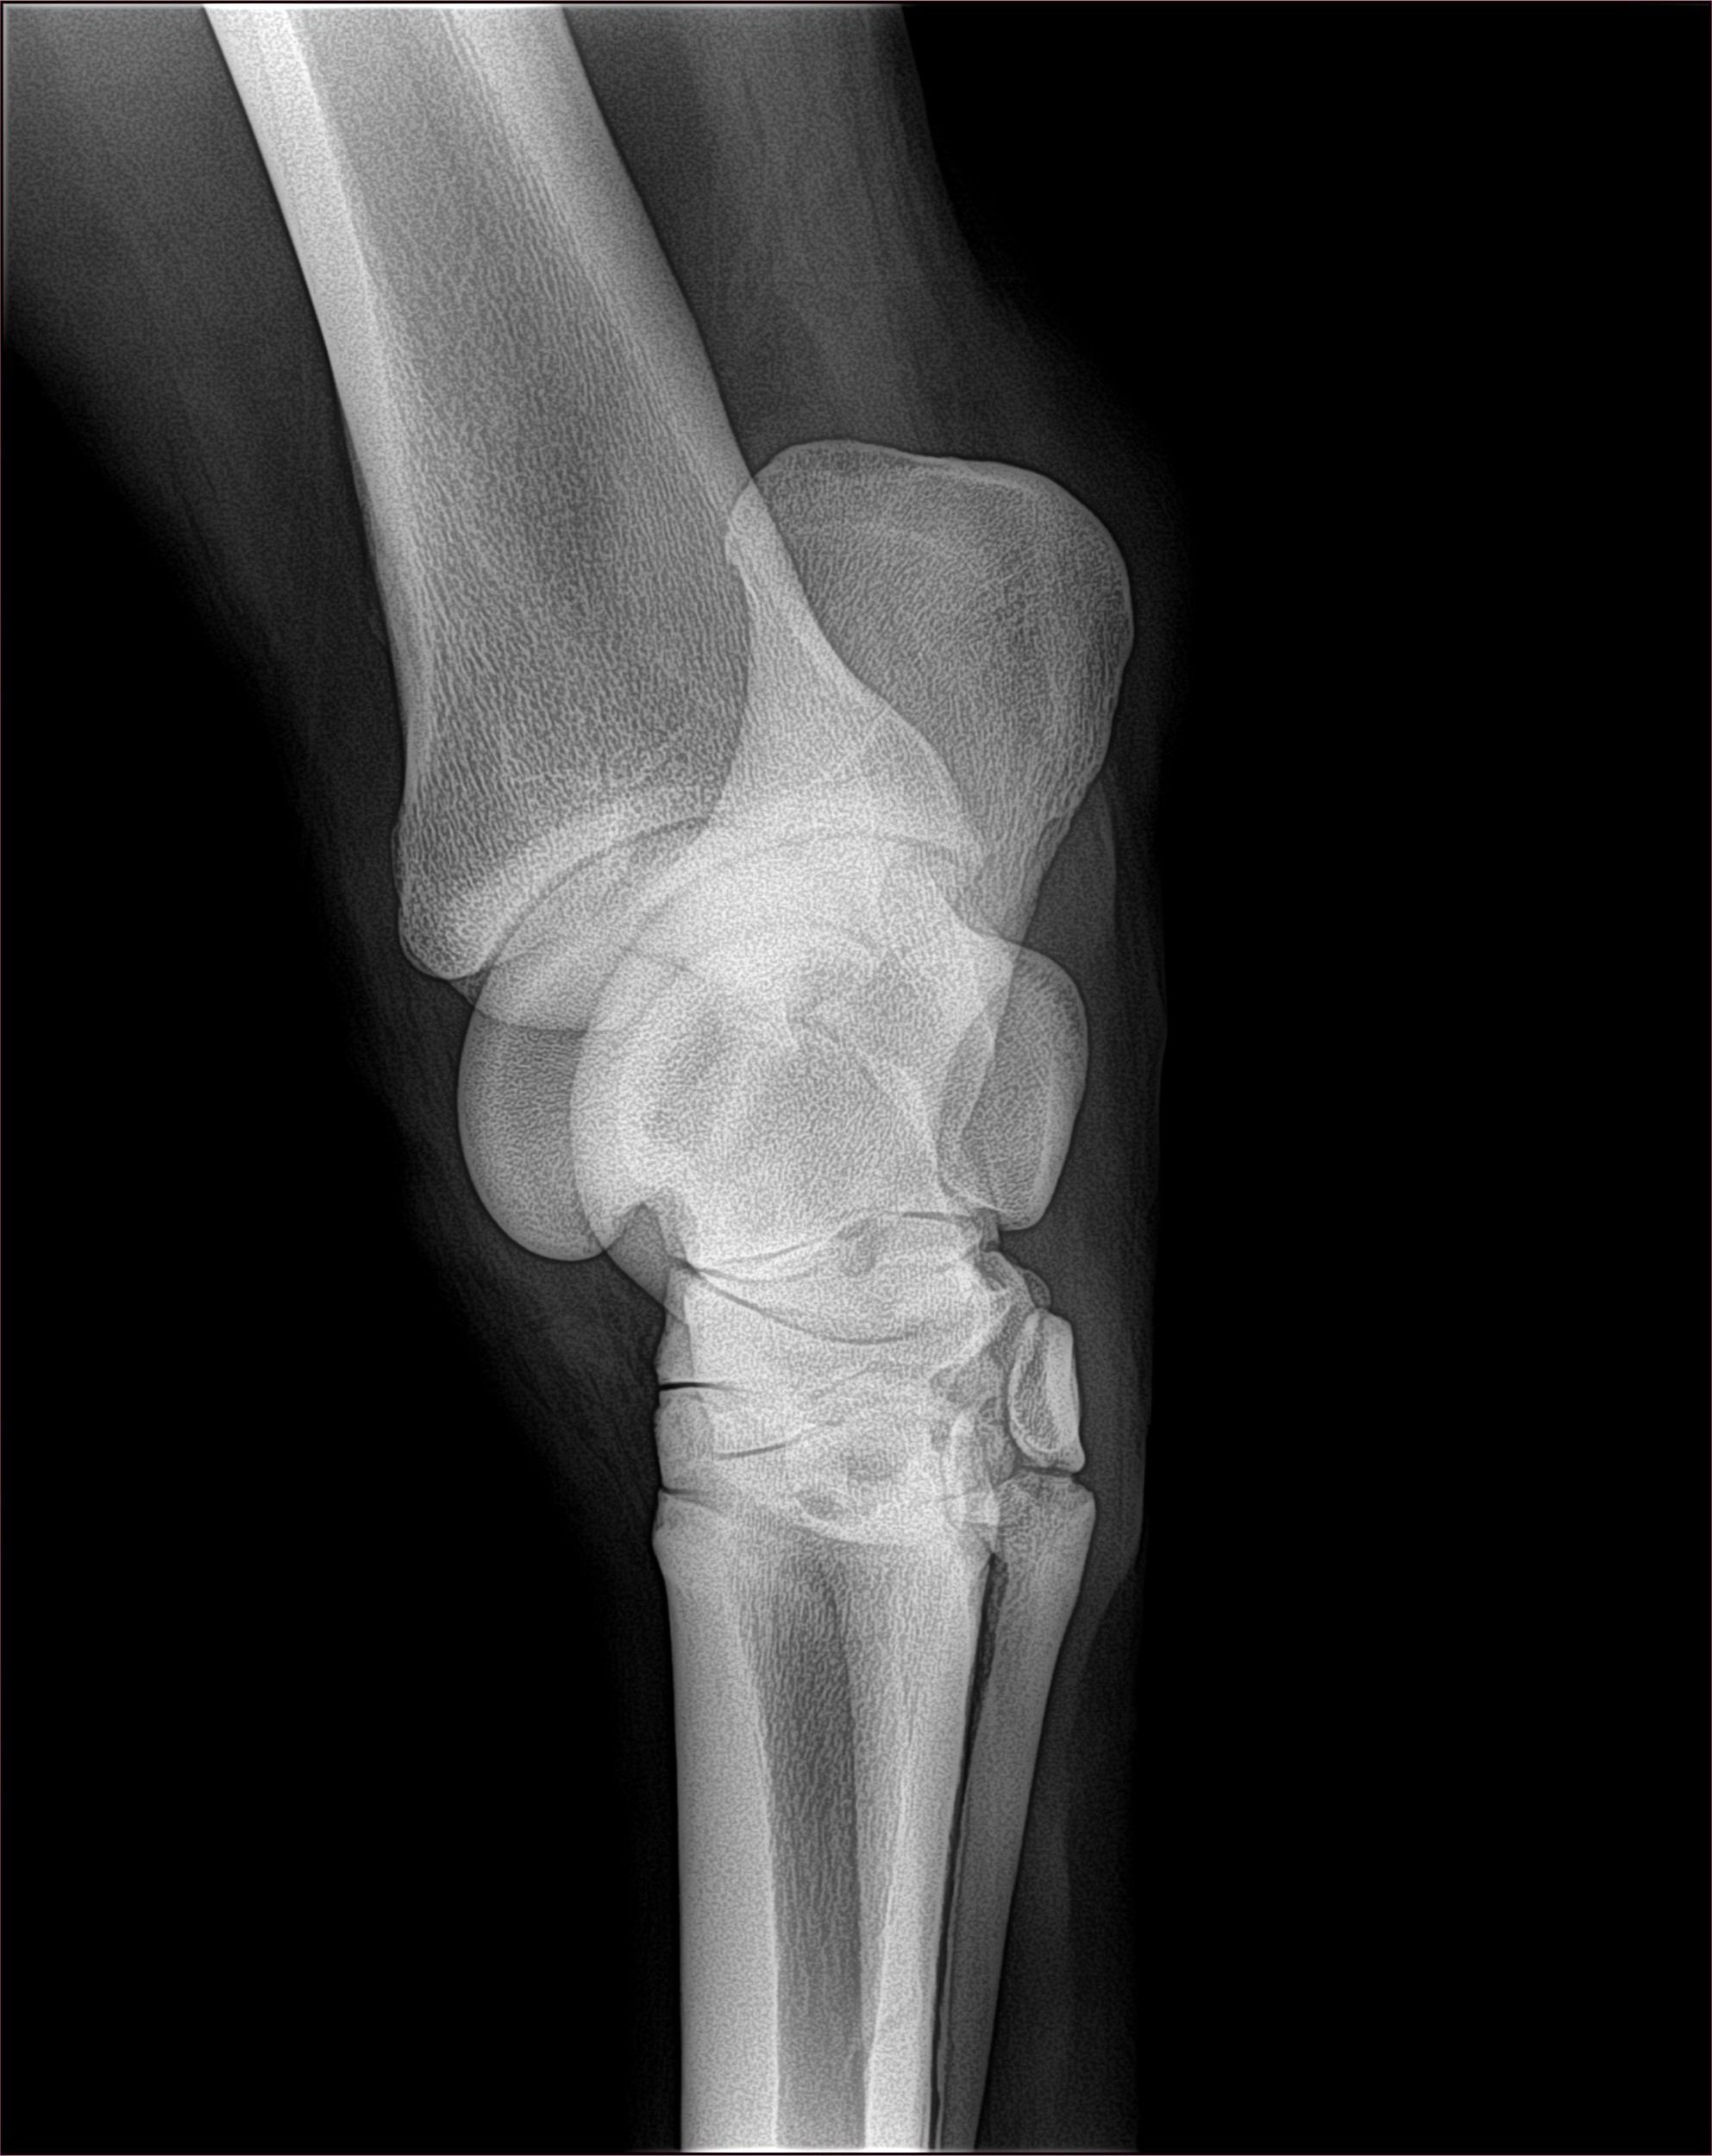

Get clear, accurate images of equine injuries

Make faster, more accurate diagnoses

Samples of X-Rays